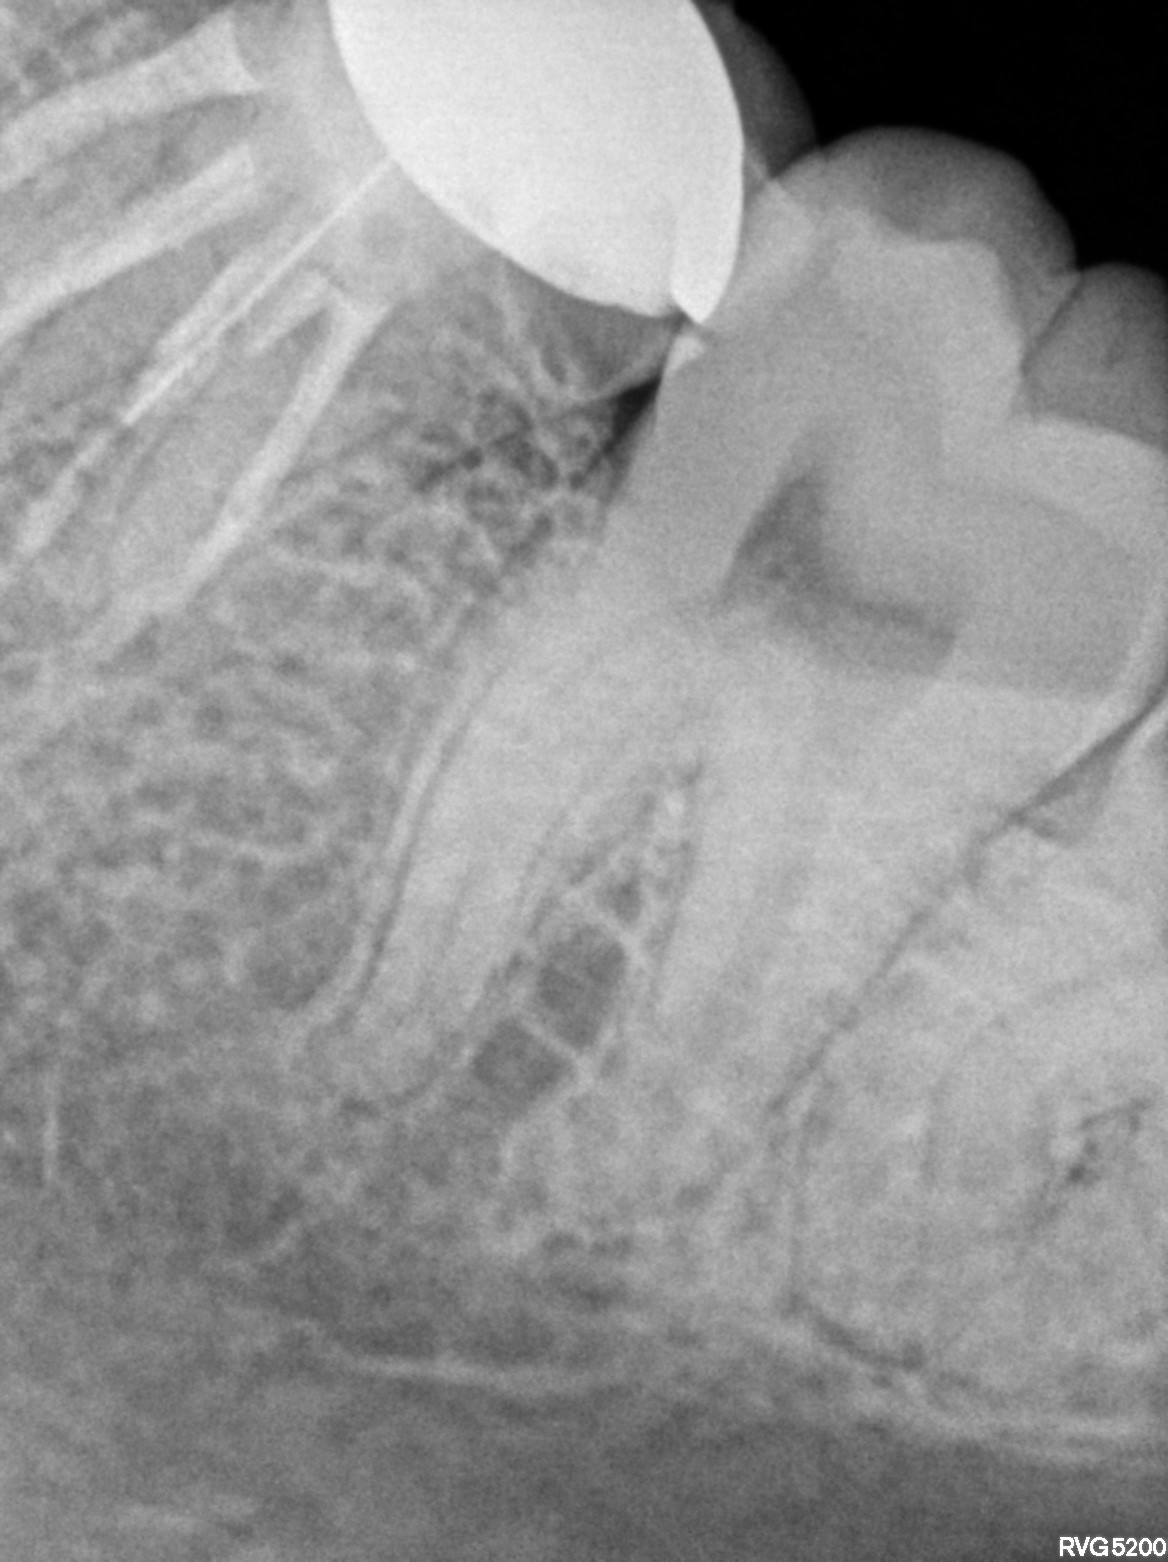

Dental Radiographs FHIR: DocumentReference · LOINC 24641-7

xray_1772899428_2.jpg

24641-7

| Necrosis of dental pulp | K04.1 | 234946006 | resolved | 2026-03-07 | adv rct with 47(5k-5500) followed by ceramic crown 3500 and surgical extn with 38 @7k-8k// extn with 48 advised only if pain persists and if pt wills | |

| Root canal treatment | 234780006 | D3330 Endodontic therapy, molar tooth | ##47, #38, #48 | 2026-03-07 | completed | adv rct with 47(5k-5500) followed by ceramic crown 3500 and surgical extn with 38 @7k-8k// extn with 48 advised only if pain persists and if pt wills | |

| 2026-03-07 21:33 | fulfilled | adv rct with 47(5k-5500) followed by ceramic crown 3500 and surgical extn with 38 @7k-8k// extn with — Dr Hani | |